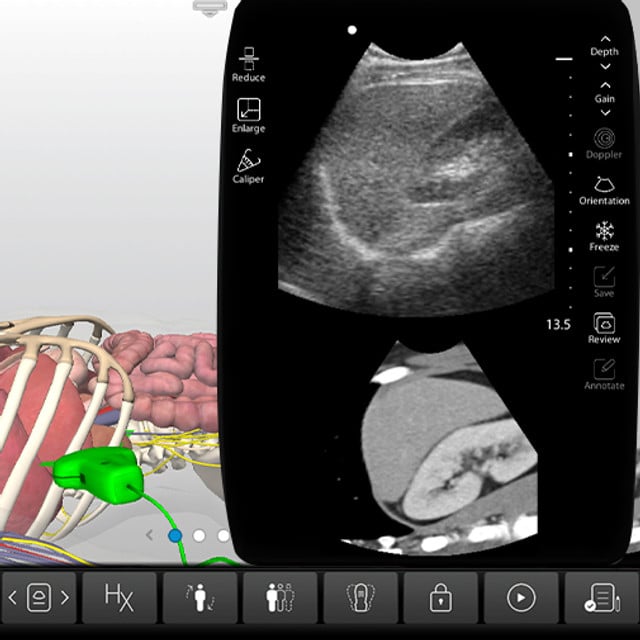

Hands-On Scanning in the SonoSimulator®

After completing the courses, practice with real pathologic cases in our SonoSimulator®. Simulate the experience of scanning real pathologic cases on your computer.

Develop ultrasound image acquisition and interpretation skills with our patented SonoSimulator®. Our innovative platform provides hands-on practice with on-screen probe guide and virtual tutor on-demand overcoming the primary barriers to learning how to scan and read ultrasound.

An on-screen probe guide provides precise image acquisition guidance & virtual layers help develop visuospatial skills

Ultrasound experts narrate key findings & provide imaging tips / real-time feedback

- Special Case Features: Additional Abdominal CT imaging, Anatomic Layer Removal